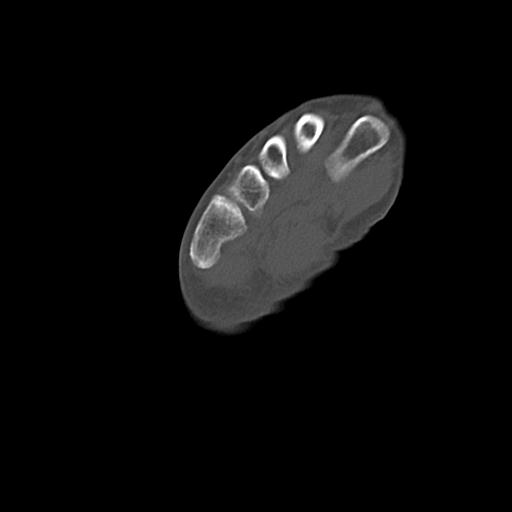

46666 1/23 両股正面+軸と右手関節 2R 76歳女性 右橈骨遠位端

46666 1/28 両股正面+軸と 1/26 右手関節 2R 76歳女性 右転子部骨折